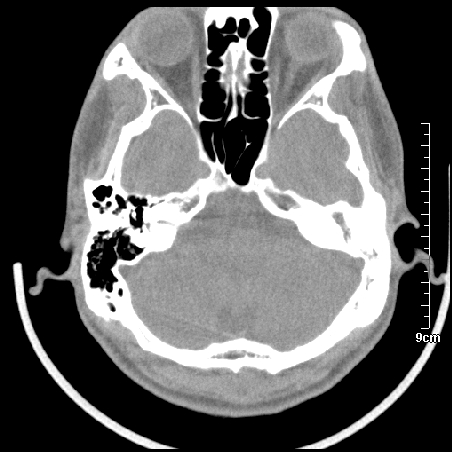

病例2

m/27

胆脂瘤是是以鳞状上皮内衬充满角质化碎片的囊,随着角化屑片的不断堆积,肿块逐渐增大,胆脂瘤可为先天性(2%)或后天性(98%)。胆脂瘤有感染史。中耳内的鳞状上皮通常有外耳道的上皮通过一鼓膜的缺损移行至中耳,其他的原因包括鳞状上皮化生。由于欧氏管的功能不全所引起的中耳负压可产生上鼓室鼓膜松弛部的牵引性开袋。继而发展成胆脂瘤。成年人胆脂瘤时乳突常发育差,而儿童常有广泛性乳突气化,这种气化可导致胆脂瘤的更广泛的乳突扩散。后天性胆脂瘤患者大多数存在骨质破坏。

松弛部胆脂瘤有中央性穿孔或后上部牵引口袋所致。紧张部胆脂瘤经常侵蚀听小骨并引起传导性耳聋。

中耳胆脂瘤有两个重要并发症:一是面神经管的水平段受暴露,二是外侧半规管受侵蚀产生瘘管。面神经在ct上难以显示或不可能显示,除非其周围有空气包绕或有良好轮廓的骨性覆盖。胆脂瘤还可合并感染,产生于急性中耳炎.乳突炎所描述的那些合并症。

左侧慢性中耳炎伴胆脂瘤形成。

左中耳乳突炎合并胆脂瘤形成